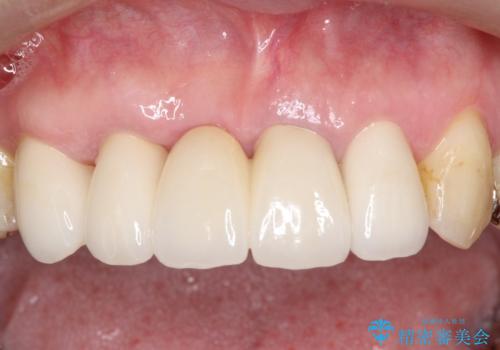

矯正を併用した前歯のセラミックブリッジ治療

1年程度の治療期間が必要となりましたが、仕上がりには患者様に満足していただけました。